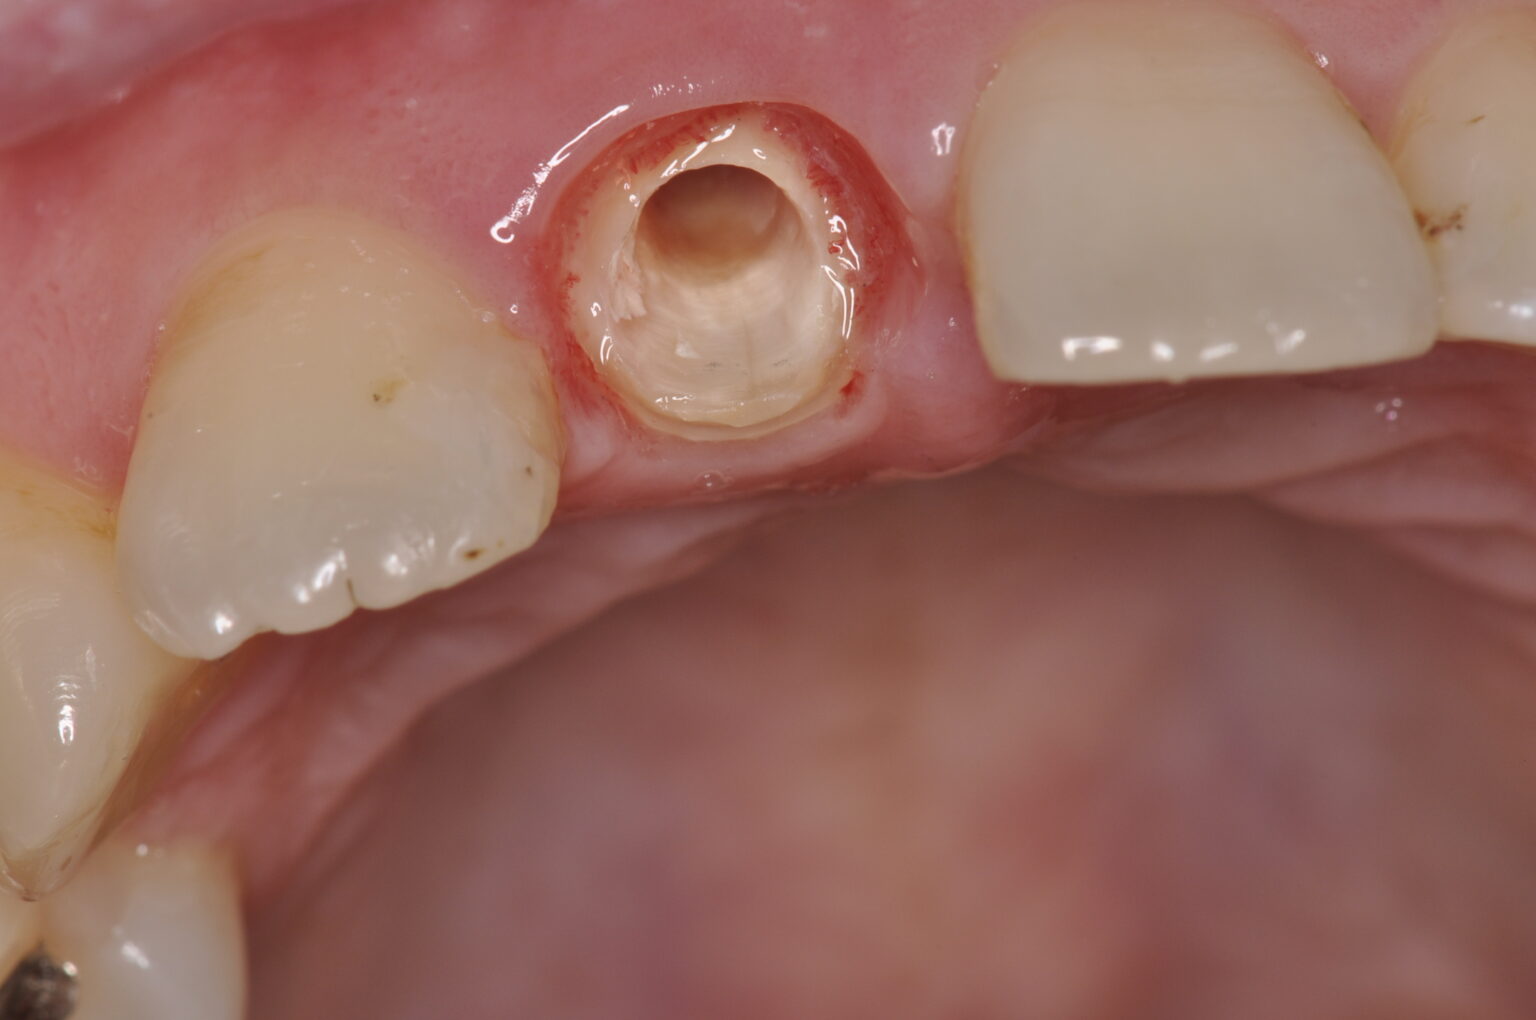

症例写真

破折線が見えます。